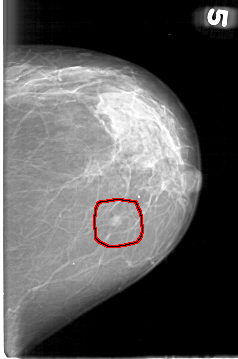

FILE: D_4095_1.LEFT_MLO.OVERLAY

TOTAL_ABNORMALITIES 1

ABNORMALITY 1

LESION_TYPE MASS SHAPE ROUND MARGINS OBSCURED

ASSESSMENT 0

SUBTLETY 4

PATHOLOGY BENIGN

TOTAL_OUTLINES 1

BOUNDARY

LEFT_MLO LINES 5281 PIXELS_PER_LINE 3376 BITS_PER_PIXEL 12 RESOLUTION 43.5 OVERLAY